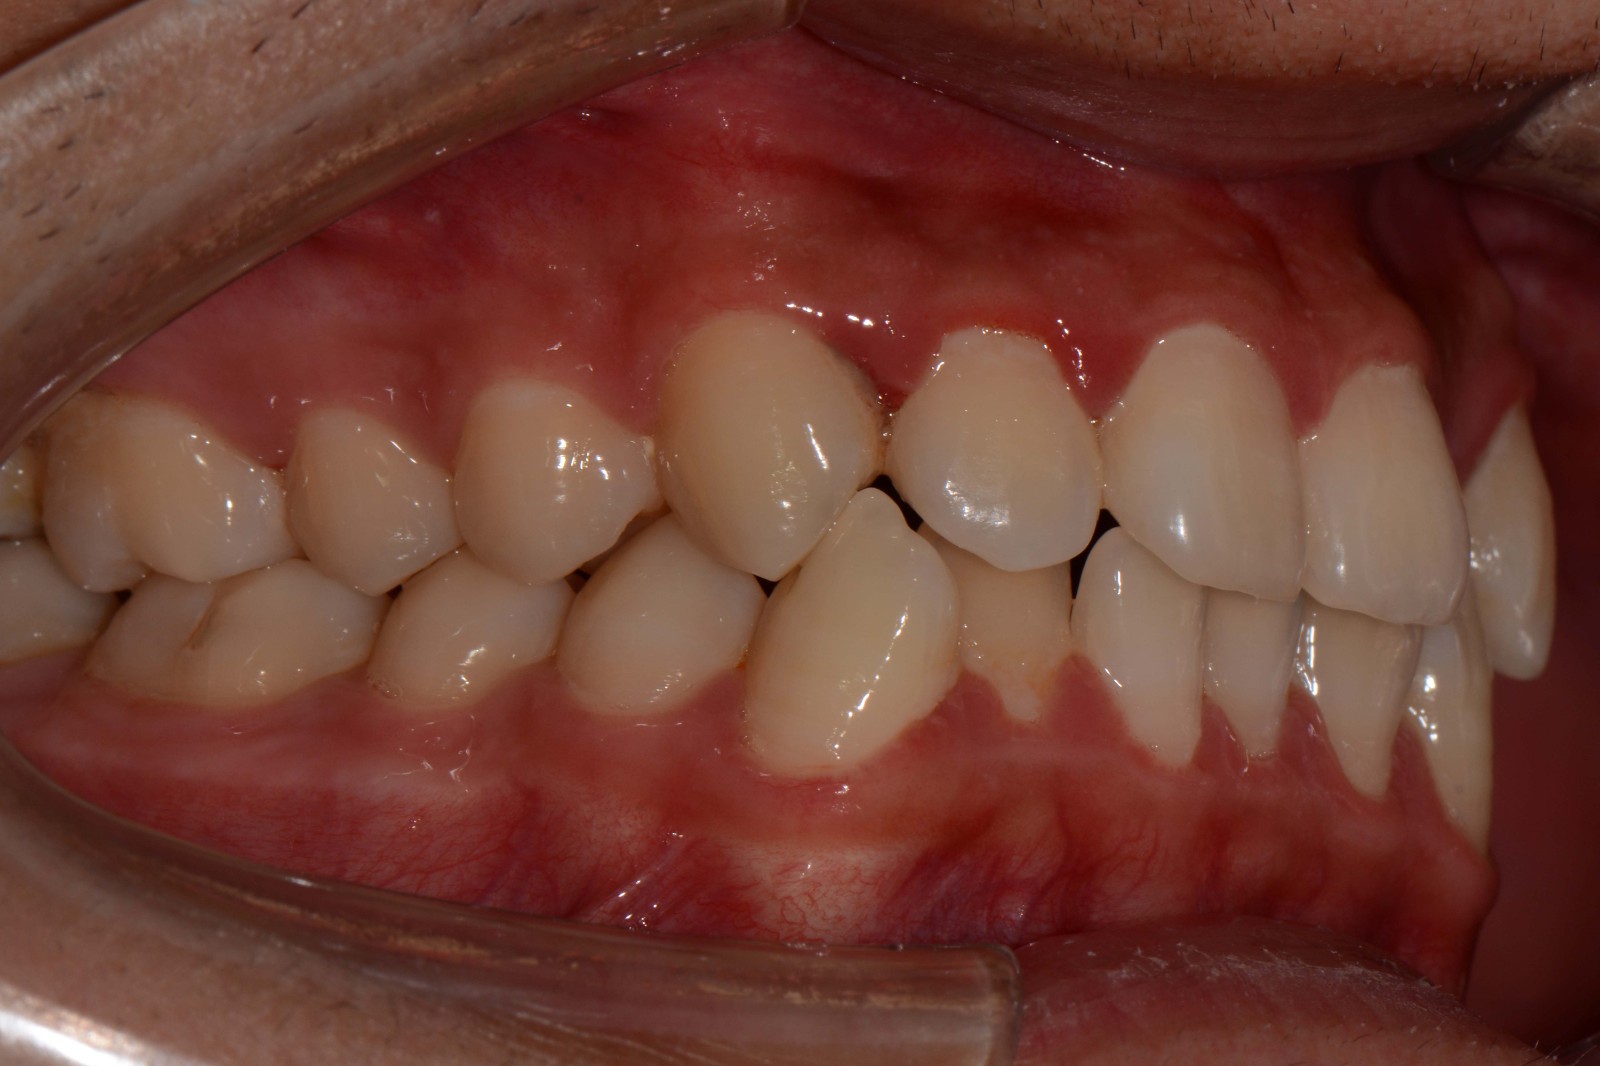

检查:拍摄口内面像照片,拍摄全景片侧位片,口扫,上下颌I-II度拥挤,中线不齐,局部反合,磨牙基本中性关系,上下前牙比较直立。

矫治前: